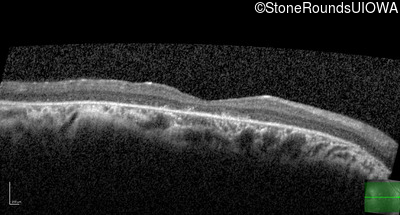

Optical Coherence Tomography - Left - 20/40 -1

Exemplar / OCT Stack

OCT Stack